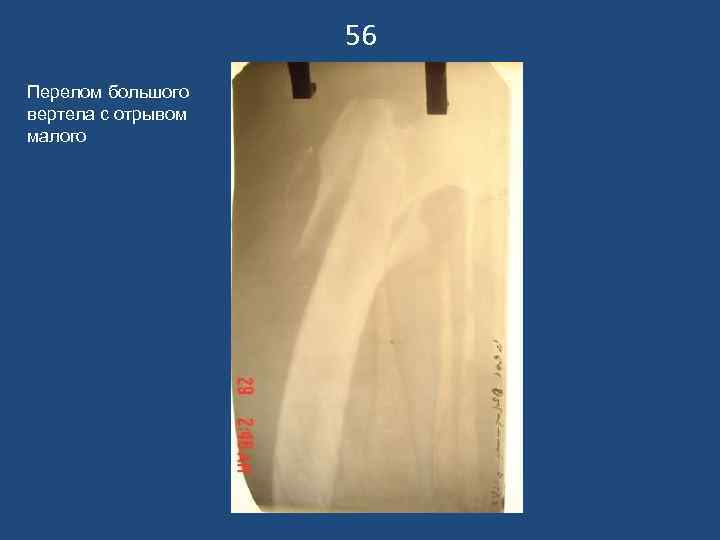

56 Перелом большого вертела с отрывом малого